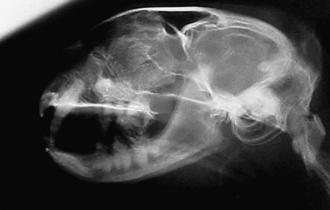

Radiography

Radiographic imaging or CT is always performed before rhinoscopy. Rhinoscopic iatrogenic hemorrhaging and irrigation fluid used during the procedure will distort tissue and create fluid densities that can influence the findings in any radiographic study. Nasal radiographs can be performed in most hospitals and, with practice, can be very useful in the localization and characterization of nasal and nasopharyngeal disease.5 Nasal radiographs require general anesthesia and special patient positioning. Most commonly performed are 30-degree beam-angled open-mouth ventrodorsal and straight lateral views. The open-mouth view provides a complete, symmetrical image of the nasal cavity without superimposition of the mandible. Tumors typically show asymmetrical opacities and turbinate destruction (Figure 19-6). Turbinate destruction is also seen with fungal rhinitis. The straight lateral view allows evaluation of the nasopharynx and frontal sinuses (Figure 19-7). Further study of the frontal sinuses is achieved with a rostrocaudal tangential view (Figure 19-8). This allows comparison of the left and right frontal sinuses as the cavities are superimposed on the lateral view. Dental films of the maxillary arcade are sometimes needed to rule out tooth root abscesses and oronasal fistulae. MRI and CT scans are becoming more commonly available and provide better detail of the nasal, nasopharyngeal, and sinus cavities and cranial vault anatomy compared with standard radiography.6,7 Advanced imaging via MRI and CT, although considered state of the art, assist in description and localization of diseased tissue but have not yet produced results specific enough to eliminate the need for rhinoscopy8,9 (Figures 19-9 through 19-11) (Table 19-1).

image

Figure 19-6 Canine open-mouth ventrodorsal view with right-sided destructive soft tissue mass; nasal osteosarcoma.

Figure 19-7 Canine tangential sinus view with right-sided frontal sinus soft tissue opacity; nasal osteosarcoma.

Figure 19-8 Feline lateral skull radiograph with nasopharyngeal mass present.